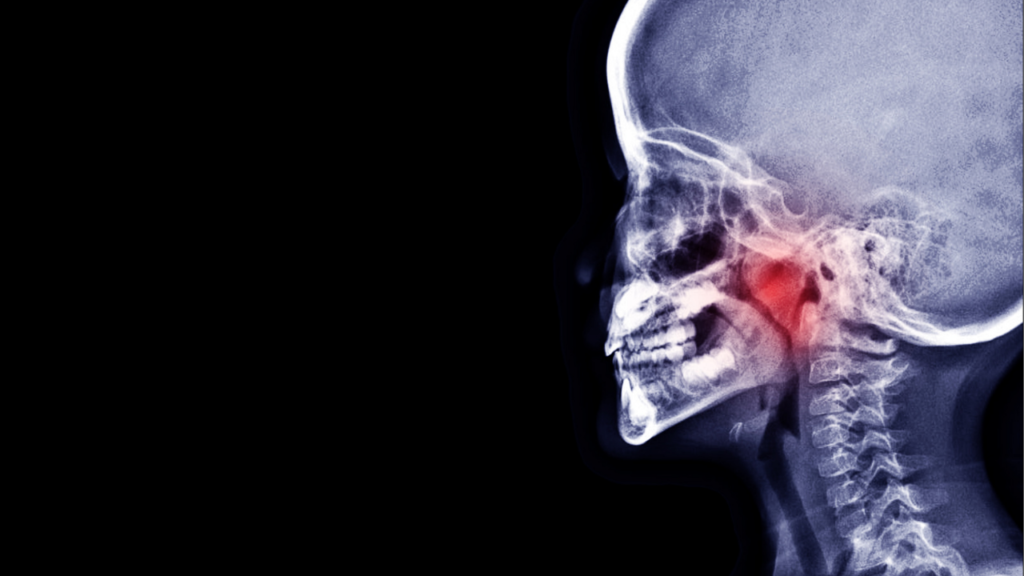

後鼻漏とは?鼻水が喉に流れて不快な症状に

毎日、鼻水が喉に流れて不快感や咳が止まらない――。

このような「後鼻漏(こうびろう)」の症状は、実は漢方薬で根本的な改善が期待できるのをご存知でしょうか?